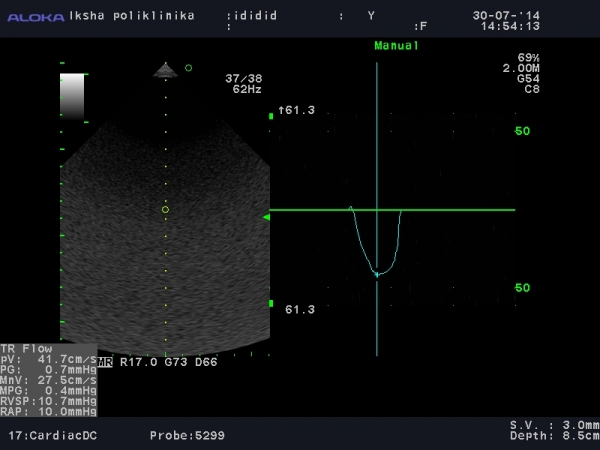

Прикрепляю две картинки. На них видно что умеет мой софт для трикуспидального:

Спасибо, это стандартные измерения на трикуспидальном клапане.

Но мой врач, считает что необходимо мерить поток на трикуспидальном как на митральном.